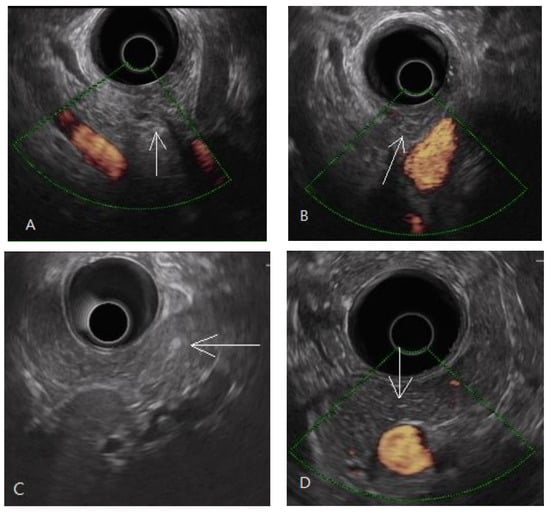

Among the 13 patients with EUS-diagnosed early chronic pancreatitis, there were altogether 45 counts of the four criteria of pancreatic parenchymal fibrosis: lobularity with honeycombing (n = 2), lobularity without honeycombing (n = 8), hyperechoic foci without shadowing (n = 12), and stranding (n = 23). According to pancreatic anatomic separation, the ratios of these four criteria in different locations were 53% in the head (including neck, and uncinate process), 38% in the body, and 9% in the tail, as shown in Figure 4.

Figure 4.

A total of 45 counts of the 4 EUS criteria of pancreatic parenchymal fibrosis in the 13 patients with EUS-diagnosed early chronic pancreatitis; (A) the ratio of EUS criteria counts in pancreatic head (including neck, uncinate process), body, and tail; and (B) the counts of each EUS parenchyma criteria for pancreatic fibrosis. EUS: endoscopic ultrasonography.